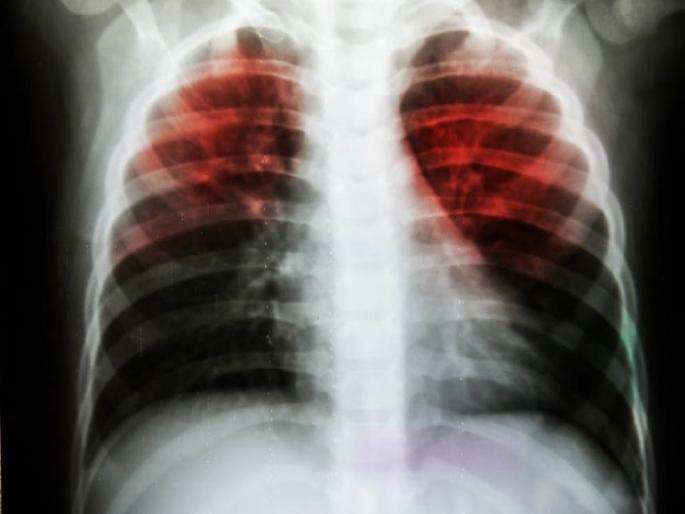

लातूर : मधुमेह, धुम्रपान, कमी वजन अशा कारणांमुळे जिल्ह्यातील १८ वर्षांपुढील ३ लाख २८ हजार ५०६ व्यक्ती क्षयरोगाच्या अति जोखमीच्या कक्षेत असल्याचे सर्वेक्षणात आढळून आले आहे. त्यामुळे अतिजोखमीतील व्यक्तींनी आरोग्याची अधिक काळजी घेणे गरजेचे ठरत आहे.

क्षयरोगाचा संसर्ग हा थुंकी, खोकल्यामुळे हवेतून होतो. दोन आठवड्यांपेक्षा जास्त खोकला, ताप, भूक मंदावणे, वजन कमी होणे, थुंकीवाटे रक्त पडणे, काखेत अथवा मानेभोवती गाठ येणे अशी क्षयरोगाची लक्षणे आहेत. क्षयरोगाचा संसर्ग रोखण्यासाठी लक्षणे दिसणाऱ्या व्यक्तींची लवकरात लवकर तपासणी करुन उपचार करणे महत्त्वाचे ठरते.